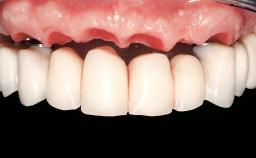

Replacement of Two Teeth in a Partially Dentate Posterior Maxilla with a Fixed Dental Prosthesis Using a Conventional Loading Protocol

In September of 1995, a 64-year-old female patient presented to our clinic with a distally shortened arch in the left maxilla and the desire for a fixed rehabilitation. The patient’s medical history did not reveal any major issues, and she did not take any significant medication. She was a non-smoker and did not report any allergies.The patient wished to restore her chewing function on the left side, which was severely compromised due to the missing teeth 25, 26, and 27. The antagonistic lower teeth were present and in acceptable condition.